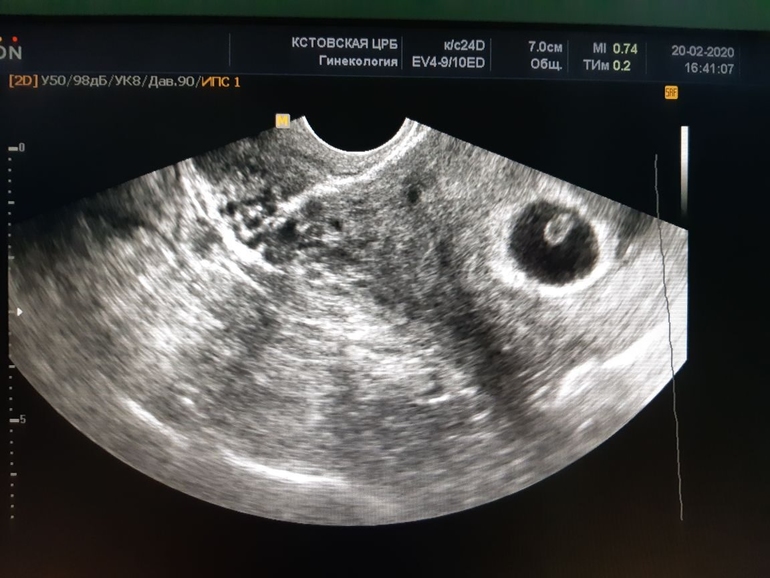

5 недель беременность не обнаружили по УЗИ(((

В 5,4 нед не увидели, сказали придти через 10 дней Потом все нашли Не переживайте! Срок ещё маленький

5 недель и 6 дней увидели толко плодное яйцо. Поставили анэмбрионию. Ровно через неделю в 6.6 нашли сердцебиение и эмбрион